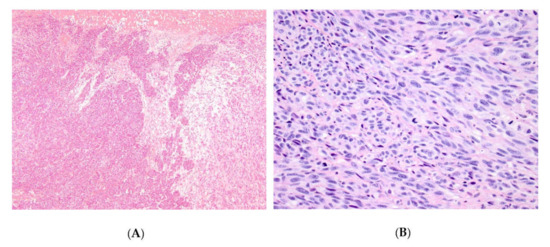

3.1. Expression of PARP1, IDO1, and PD-L1 in Mucosal Melanoma Cells.